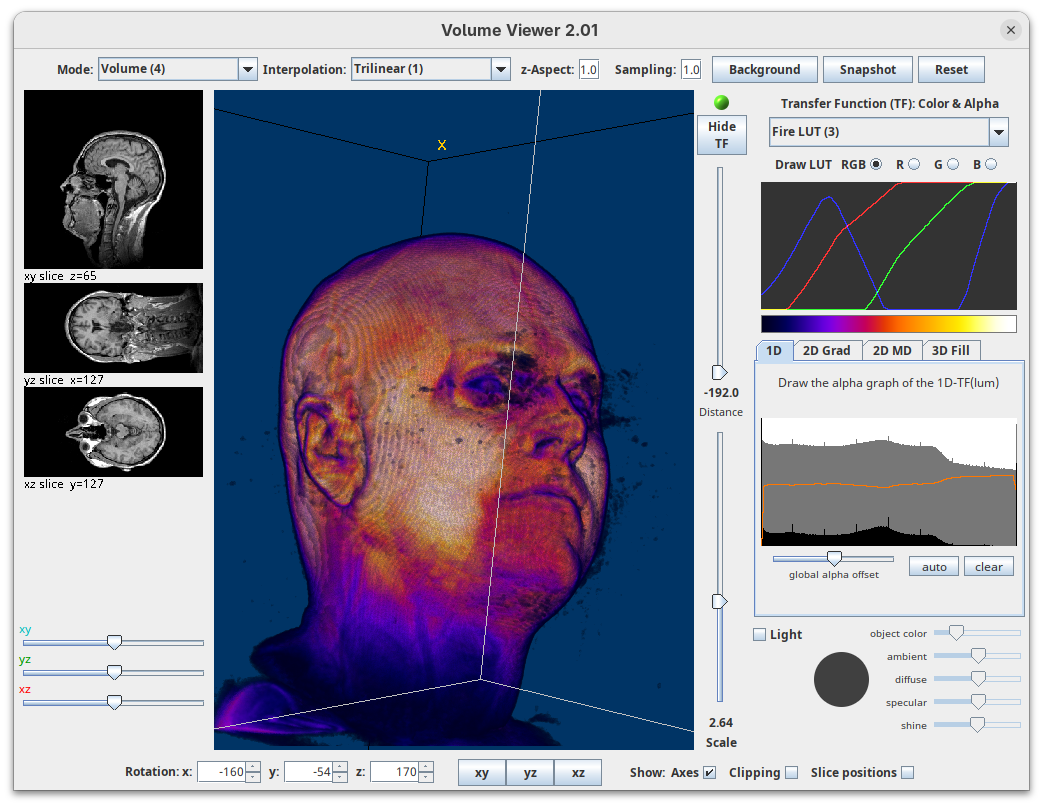

Volume Viewer

Volume Viewer is a more powerful plugin for 3D visualization as it supports slicing, projections, and rendering. The interface is interactive and intuitive to use. To open it:

- Go to

Plugins>Volume Viewer. The main interface will open in theSlicemode.

- Click around and move the sample to see optical sections from different angles.

- Then, activate the

Volumemode to render the sample’s surface in 3D and explore it as well, playing with the different rendering parameters.

Volume Viewer also provides a way to take snapshots of the current view.